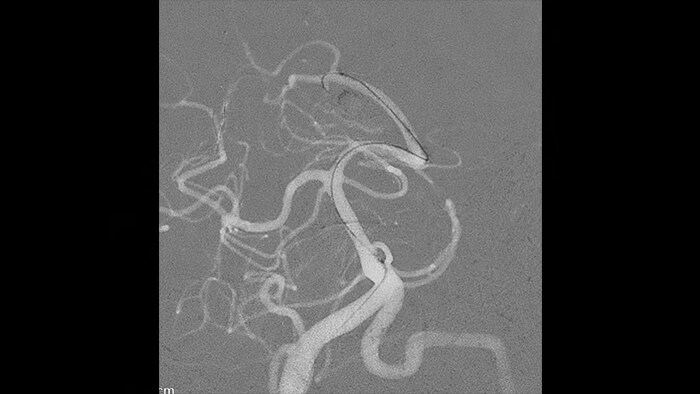

SmartCT Roadmap biedt een live 3D-beeldoverlay die kan worden gesegmenteerd om het beoogde bloedvat en de laesies te benadrukken, waardoor snelle katheternavigatie wordt ondersteund. De SmartCT Roadmap overlapt een 3D-reconstructie van de vaatboom, de vaatsegmenten of annotaties met live fluoroscopie.

In de Roadmap Pro-lijmmodus worden al geëmboliseerde vaten uitgefilterd, zodat u zich kunt concentreren op wat u injecteert en hoe het zich verspreidt.